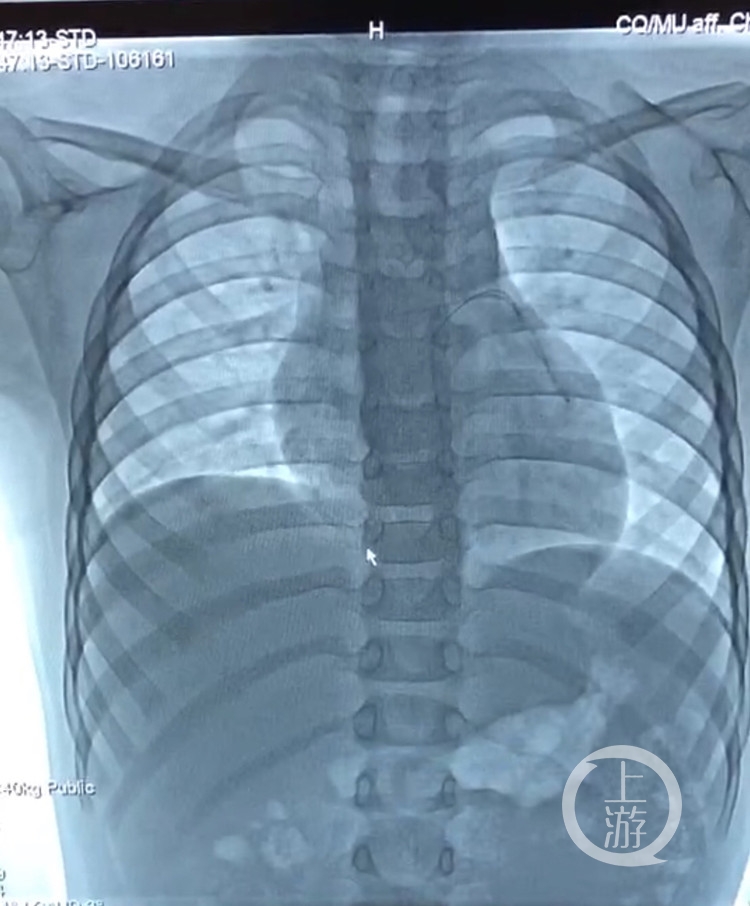

4月11日上午8时,心内科联合胸心外科治疗团队、麻醉科及放射科准备为患儿实施介入微创手术。易岂建指挥监控手术进程,李谧教授担任主刀医生。手术中在透视下可见PICC导管扭曲分布于心腔及肺部血管,由于PICC导管断端在体内留置时间长,在牵拉过程中有再次断裂的可能,需要精细的手法和多年心导管介入治疗的经验,凭借十几年的手术经验,李谧教授从容不迫的运用手中的导管到达心脏内,利用圈套器抓住断裂的PICC导管远端,随着圈套器的牵引顺利将异物取出体外,手术非常成功。